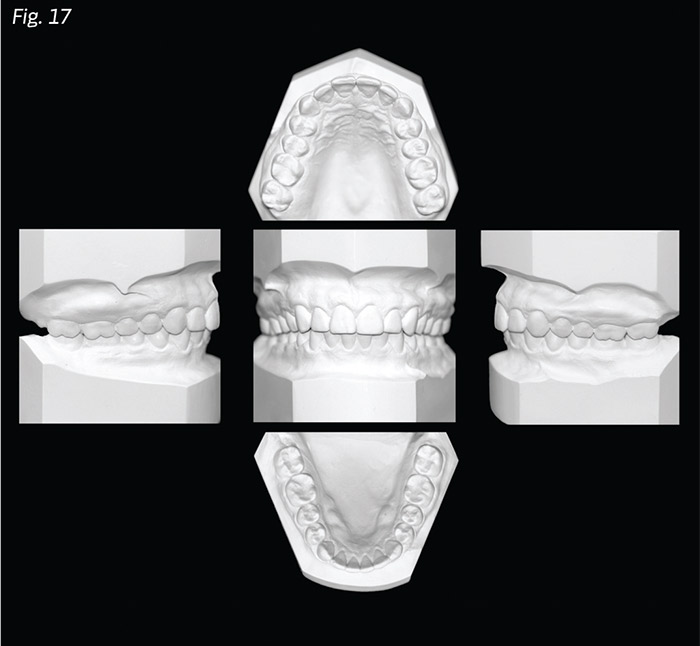

When patients present challenging vertical dimension problems, the orthodontist and restorative dentist should work together to diagnose and treatment plan which teeth should be intruded, if orthognathic surgery or posterior restorations are necessary, which teeth will be restored, how long the teeth should be maintained prior to restorations, if gingival margins will be altered in the orthodontic alignment, and how all of the planned tooth movement will affect the patient's facial aesthetics on full smile (Figs. 16a-b) and final occlusion (Fig. 17).